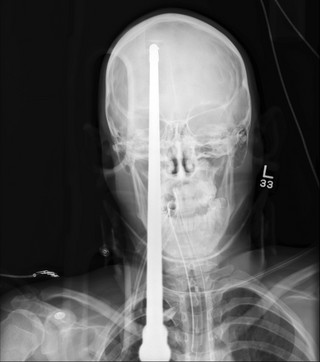

Οι ακτινογραφίες δείχνουν πώς η λόγχη διαπέρασε το κρανίο και τον εγκέφαλο του αγοριού. Ο Yasser Lopez κολυμπούσε με φίλους του σε λίμνη στη Φλόριντα όταν ένας 15χρονος φίλος του κατά λάθος απελευθέρωσε το καμάκι ενώ «όπλιζε» το ψαροντούφεκο.

Το καμάκι χτύπησε τον Lopez μερικά εκατοστά πάνω από το δεξί του μάτι, καρφώθηκε στο κρανίο του και ακινητοποιήθηκε στο δεξί λοβό του εγκεφάλου του. Τα παιδιά σοκαρισμένα είδαν το καμάκι να μπαίνει στο πίσω μέρος του κεφαλιού του και να εξέχει από το μέτωπό του!

Αντίθετα οι γιατροί σταθεροποίησαν το καμάκι και απομάκρυναν κομμάτι μήκους 47 εκατοστών, πριν βγάλουν τις ακτινογραφίες. Χρειάστηκαν στη συνέχεια τρεις ώρες για να απομακρύνουν τη λόγχη από τον Lopez, ο οποίος νοσηλεύεται σε σοβαρή αλλά σταθερή κατάσταση.